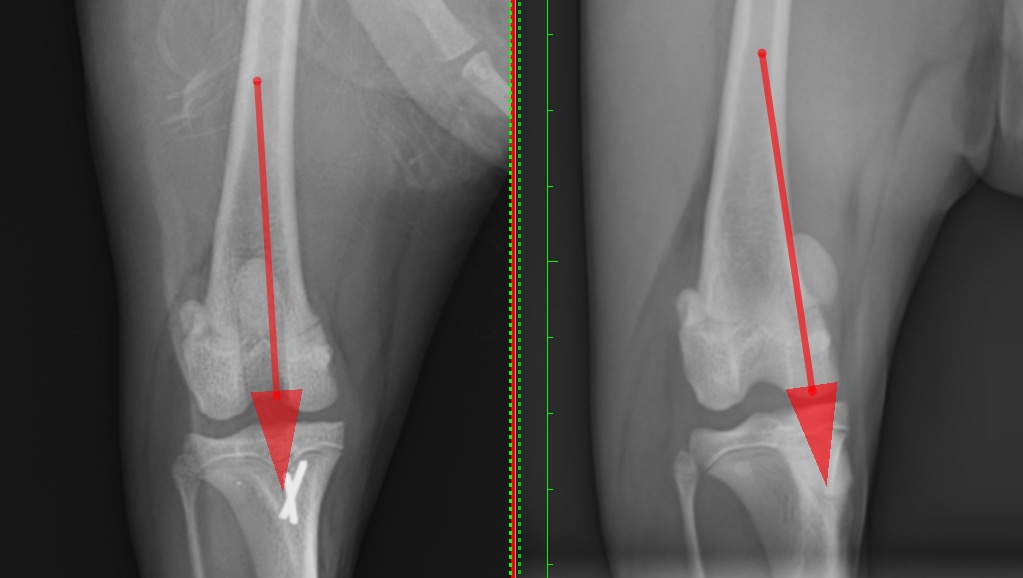

左:脛骨粗面転移術後  右:術前